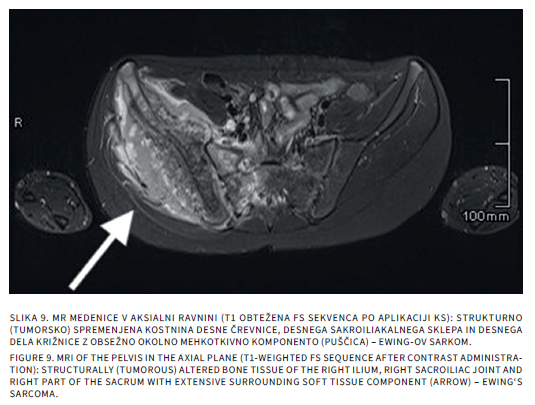

Bolečine v mišičnoskeletnem sistemu so v otroškem obdobju sorazmerno pogoste. Delimo jih na akutne in kronične, slednje trajajo več kot 3 mesece. Diferencialna diagnoza tako akutnih kot kroničnih bolečin v sklepih pri otrocih je široka. Slikovne preiskave so poleg anamneze, klinične slike in laboratorijskih izvidov pomembne v diagnostičnem postopku iskanja vzrokov bolečine. Katero slikovno metodo uporabimo najprej, je odvisno od mesta bolečine in od prizadetosti tkiva. Pri mehkotkivnih spremembah in oteklinah sklepov je prva diagnostična metoda ultrazvočna preiskava, pri sumu na prizadetost kosti pa rentgensko slikanje. Če je potrebno, sledi magnetnoresonančno slikanje ali računalniška tomografija. V prispevku bomo opisali anatomske in morfološke značilnosti otroškega skeleta, ki lahko dajejo videz patoloških sprememb ter slikovne diagnostične postopke pri akutnih in kroničnih bolečinah v sklepih.